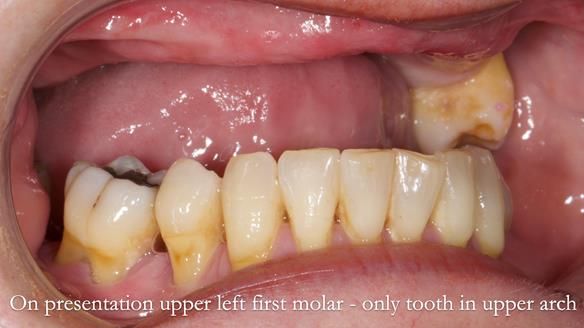

Welcome to my Newsletter 58, where I show the making and fitting of an upper gasket partial denture for Zoe (52 year old woman). This issue provides a comprehensive overview of the entire protocol workflow for this superbly retained denture.

The upper left first molar demonstrated excellent condition, with no signs of mobility, caries, or periodontal issues.

The remaining natural teeth were invaluable. I advised continuing regular appointments with her General Dentist to ensure the preservation of these natural teeth for as long as possible. I emphasised it is crucial to maintain the remaining natural teeth with meticulous daily cleaning, especially where they emerge from the gums.

The detailed clinical situation and treatment process are outlined below, with clinical work provided by me and technical work by Rowan Garstang. The treatment spanned five visits for denture fitting and one review.